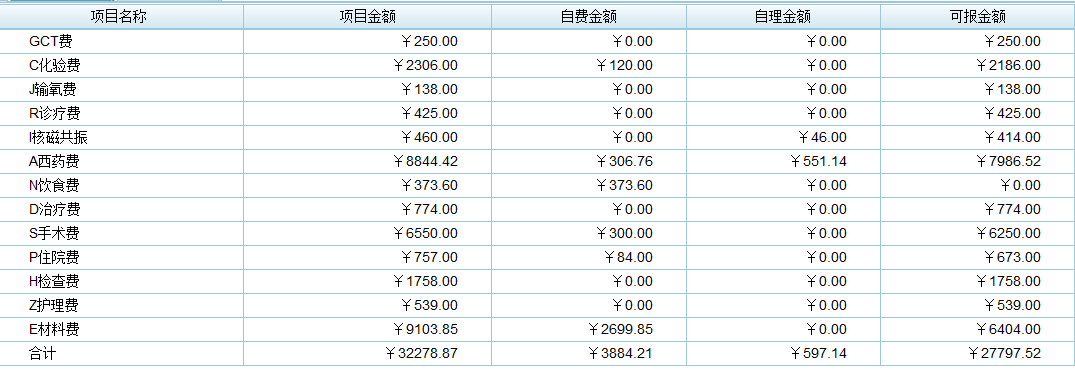

手术切除是早期肝癌安全(手术死亡率为0)、有效(5年生存率达到70%)、高性价比(报销前费用在3万元左右)的治疗方式。以下4例有乙肝病史,经定期筛查(肝脏B超和甲胎蛋白)发现的早期肝癌,手术切除后平均住院时间6天,无任何并发症,自费仅数千元。